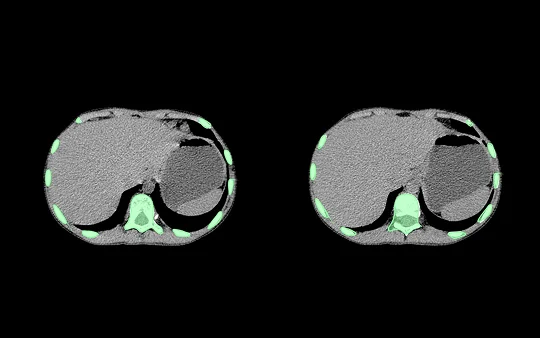

Deep learning medical imaging refers to the application of neural networks, especially convolutional neural networks, to analyze and interpret medical images. This involves training models to identify patterns in images such as X-rays, MRIs, CT scans, and ultrasounds, facilitating faster and often more accurate diagnoses.

Unlike traditional image processing, deep learning can self-learn features from large datasets, making it exceptionally effective for complex imaging tasks. With the growing availability of digitized medical data, the use of AI in medical imaging is not just valuable—it’s essential.

Deep learning algorithms can automatically detect anomalies in chest X-rays, brain MRIs, and bone fractures, significantly reducing radiologist workload.